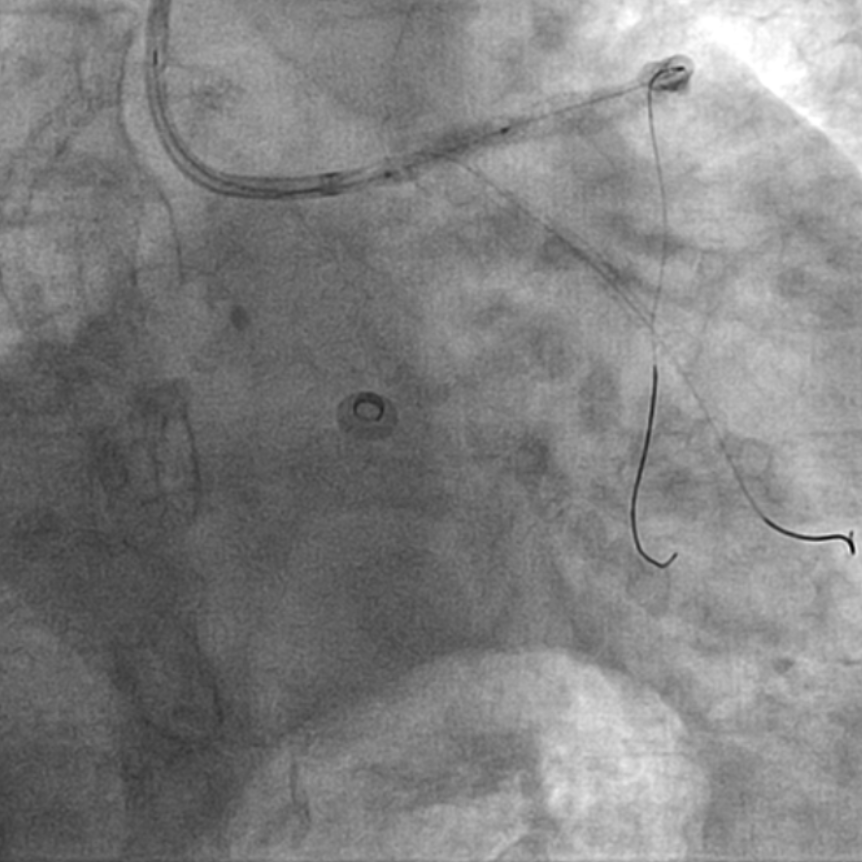

图1 外院手术过程,RCA无法扩张